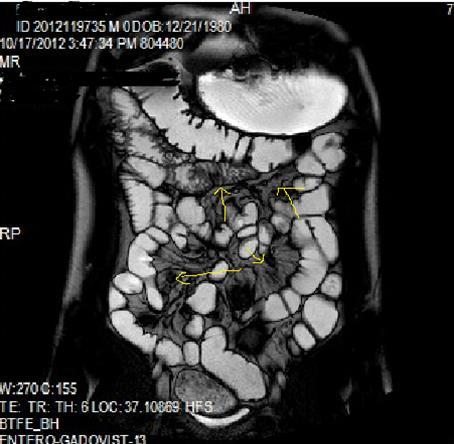

Figure 1a.Diffuse mucosal involvement and increased wall thickness with loss of valvula conniventes in the ileal segments on T2W coronal images after OCA administration, seen on 30 years old female with moderate Crohn’s disease.

Figure 1b.Diffuse bowel wall enhancement in the small intestine due to Crohn’s disease on the Post-contrast T1W coronal sequence.